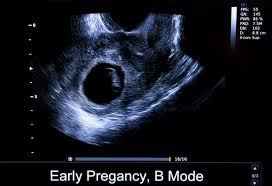

Nov 10, 2020 · how long can you carry a blighted ovum? What to do with a blighted ovum pregnancy? A blighted ovum will cause a miscarriage usually at 7 to 12 weeks of pregnancy. You have a placenta and a gestational sac, but the embryo doesn't grow. How long can a blighted ovum pregnancy last?

Feb 23, 2019 · many women with a blighted ovum have gone on to have multiple viable pregnancies. While you don't want to carry too long due to risk of infection, research suggests waiting until 9 weeks of pregnancy to intervene on a blighted ovum. A blighted ovum usually occurs between the 8th and 13th weeks of pregnancy. You have a placenta and a gestational sac, but the embryo doesn't grow. Your body understands the pregnancy is not developing properly and starts to shed blood and tissue from the uterus. What to do with a blighted ovum pregnancy? It's also called anembryonic pregnancy or empty sac. Can a blighted ovum be a positive pregnancy test?